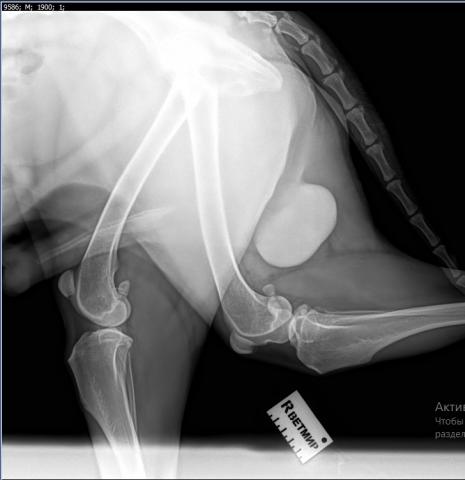

Начну с того, что не исключаю у Вашего пса дисплазию тазобедренных суставов. Думаю, что это она явилась причиной "шаркающей" походки с детства. Но в истории этой болезни она, по всей видимости, участия не принимает. Если Вы сделаете снимки суставов, то сразу выявите это заболевание. Думаю, тот факт, что собака плохо передвигалась, не связан с процессом в суставах, а с ухудшением общего состояния вследствие интоксикации, вызванной инфекционным процессом в предстательной железе. При гнойных процессах в организме животных их состояние быстро и значительно ухудшается. О происхождении абсцесса в простате ничего не могу сказать, это вопрос к ветеринарной медицине.

Мы делали комплексное УЗИ, оно есть в фотоархиве. И вот тут я прикрепляю. Плюс отдельно делали УЗИ сердца, почек, мочевого. Веде норма или почти норма.